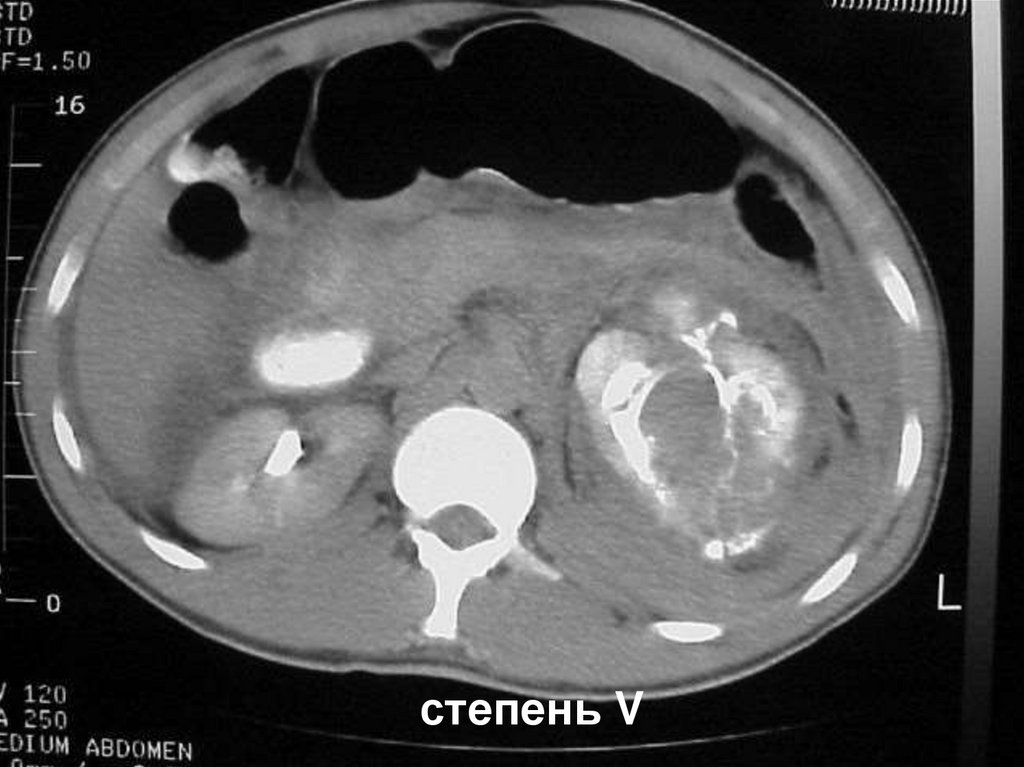

Размозжение почки или отрыв от почечной ножки

степень V